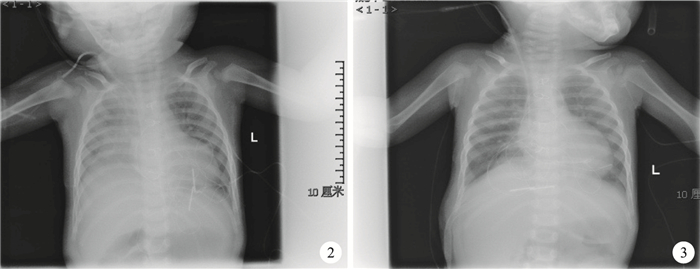

31例膈肌麻痹患兒,左側膈肌麻痹10例,右側膈肌麻痹15例,雙側膈肌麻痹6例。膈肌折疊前后胸部X線片資料:膈肌折疊前床旁胸部X線片顯示右側膈肌抬高(圖 2),膈肌折疊術后床旁胸部X線片顯示膈肌復位(圖 3)。